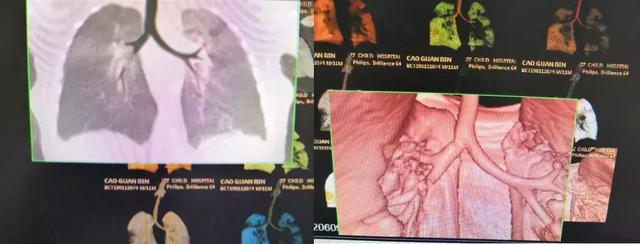

入院后 , 医生为宝宝行胸部CT , 结果提示右肺炎 。 气管重建显示右肺下叶支气管可见高密度影 , 相应管腔狭窄 。

看到这种情况 , 西区普内一病区主任孙晓敏立即决定为患儿实施支气管镜下异物探查 。

随着纤支镜缓缓进入气道深处 , 大家在右侧中间支气管开口处发现坚果样异物嵌顿 , 周围见肉芽组织生长 。

孙晓明屏气凝神 , 使用异物篮将其网住取出 , 竟是一片瓜子皮 。